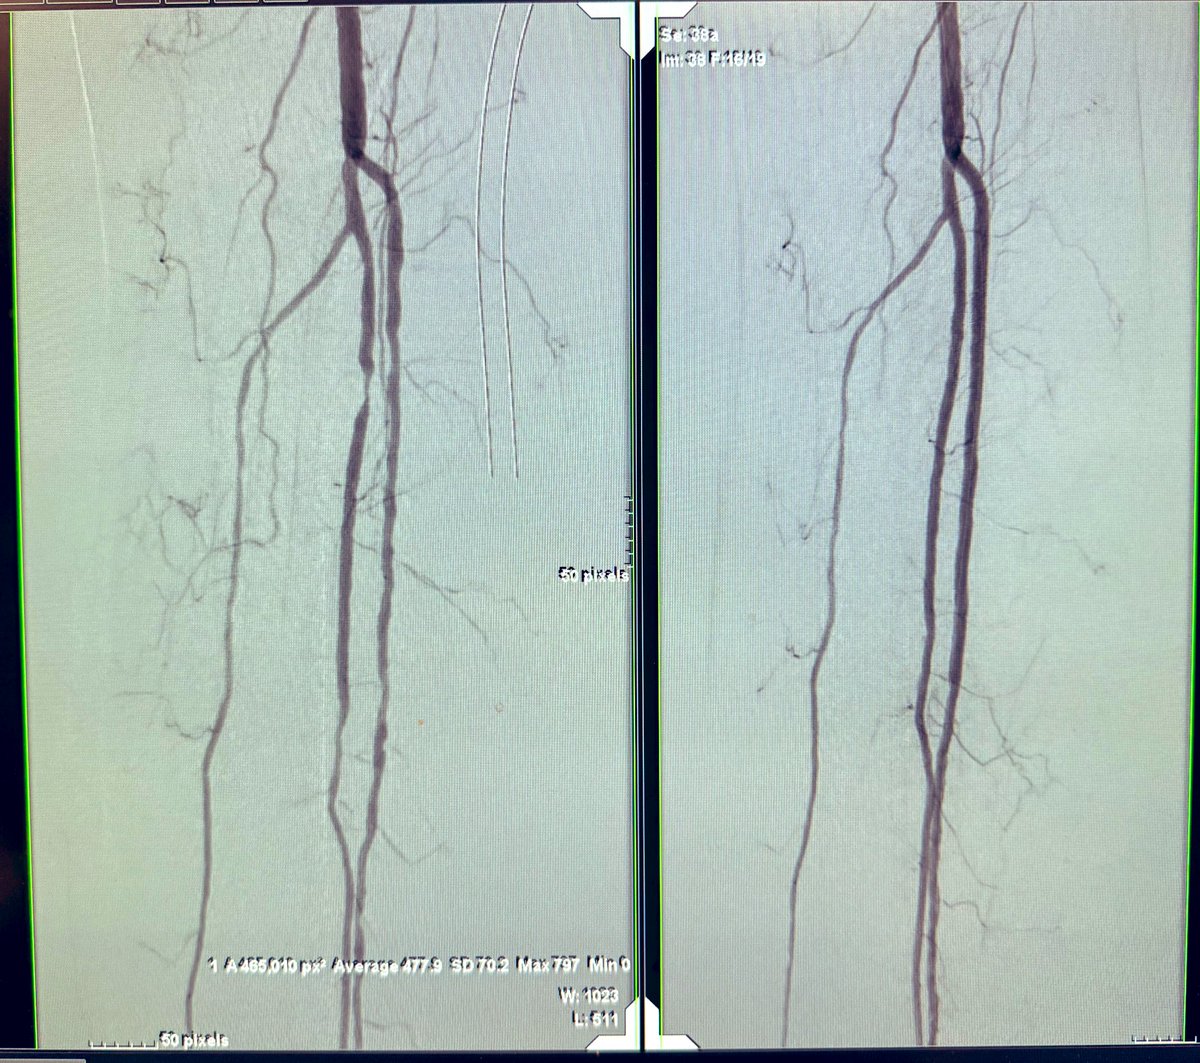

Live @MountSinaiIR Rutherford 5/6 HTN/DM/ESRD pt with non-healing wounds (forefoot and hind foot) before and after…(wanna guess what was used? 😉) now the real work begins re: Wound Care.

@kerecis @Kuldeep1926 @VascularSVS @FutureVascSurgn @AmputationSuck @AMPSymposium @TedGiffordMD 5 weeks follow up! Endo full metal jacket is open and the wound is doing well. #cltifighters @TedGiffordMD @VascularSVS @Kuldeep1926 @AmputationSuck it’s not about endo or open it’s about doing the best for the patient

English